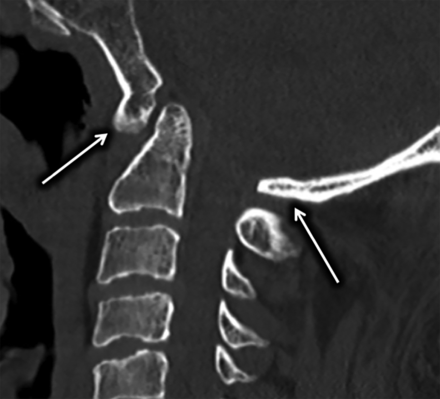

Sagittal CT of the cervical spine demonstrating congenital atlanto-occipital assimilation with 360° fusion of the C1 arch (arrows) resulting in complete absence of the FP.

Limitations in the use of the FP include congenital anomalies of the posterior arch, specifically atlanto-occipital assimilation including both complete and incomplete forms (Fig 5). Other limitations include C1 arch fracture or surgical resection. Such conditions affect the morphology of the C1 posterior arch and therefore the FP approximation to the posterior SC, making it unreliable for fluoroscopic targeting. Study limitations include the retrospective design, small subject size, potential for inconsistencies in orientation of MIP reformats, and mild variations in patient positioning within the CT scanner.